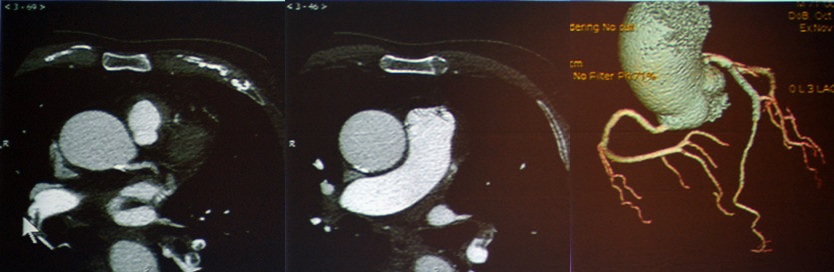

急性主动脉综合征:包括主动脉夹层、壁间血肿、穿透性溃疡。TRO可发现主动脉夹层的真假腔和内膜片。

图9 主动脉夹层Stanford B

图10-11 壁间血肿